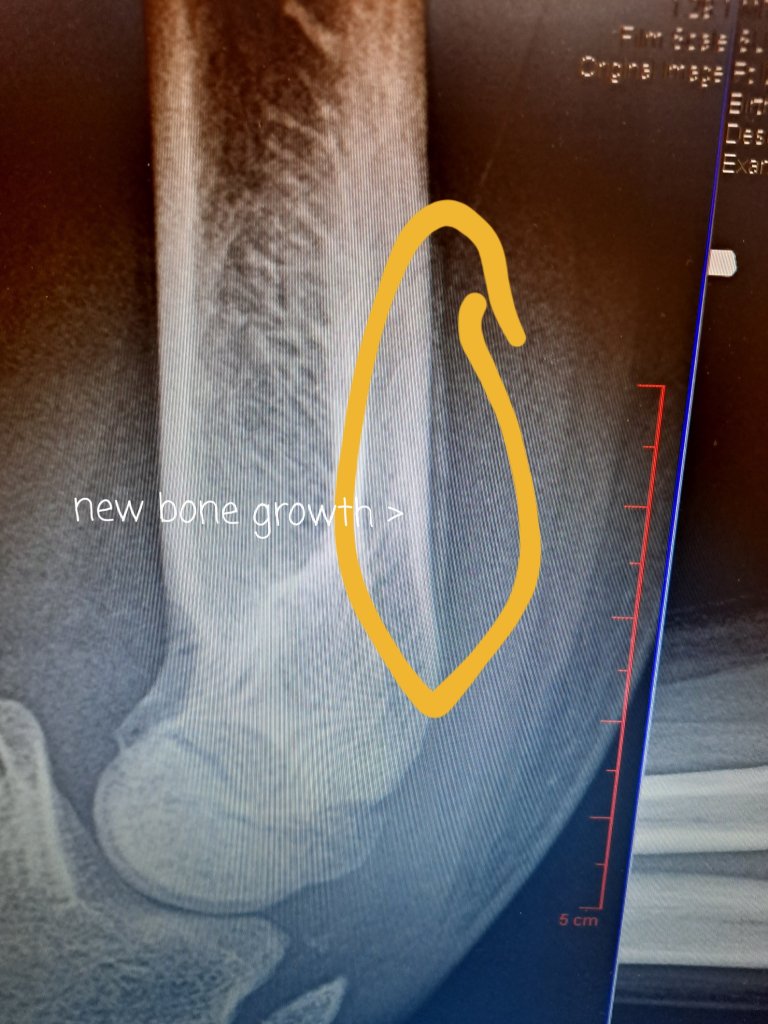

I tried to “walk it off” and went back to work like a good girl Monday and Tuesday, but it had swollen up so much on me those 2 days working, I threw up my white flag and asked my Doc (Dr V.) to check me out. One lookie ultrasound scan and she kicked me out of work for the next 2 weeks! Dang! 😕😖 Apparently I have a bad gastroc muscle. Or lots of fluid where a gastrocnemius muscle should be.

Oh yeah and I go to Jacks appointment yesterday to see if he needed his arm cast since he took a fall the day before the funeral….. Dr. R. his orthopedic Doc (who I never had met) asked about my boot and the minute I say “gastroc” he says “I know exactly who you are! Dr V. and I talked about you yesterday! I have something for you.” and gave me a wedge for my boot. Haha, embarrassing. side-note: Jack did not need a cast, cause…. super-bones!